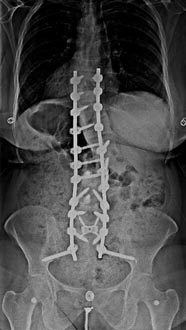

59 year old woman with Scholiosis with severe back pain.

1 year postop from surgery and pain free.